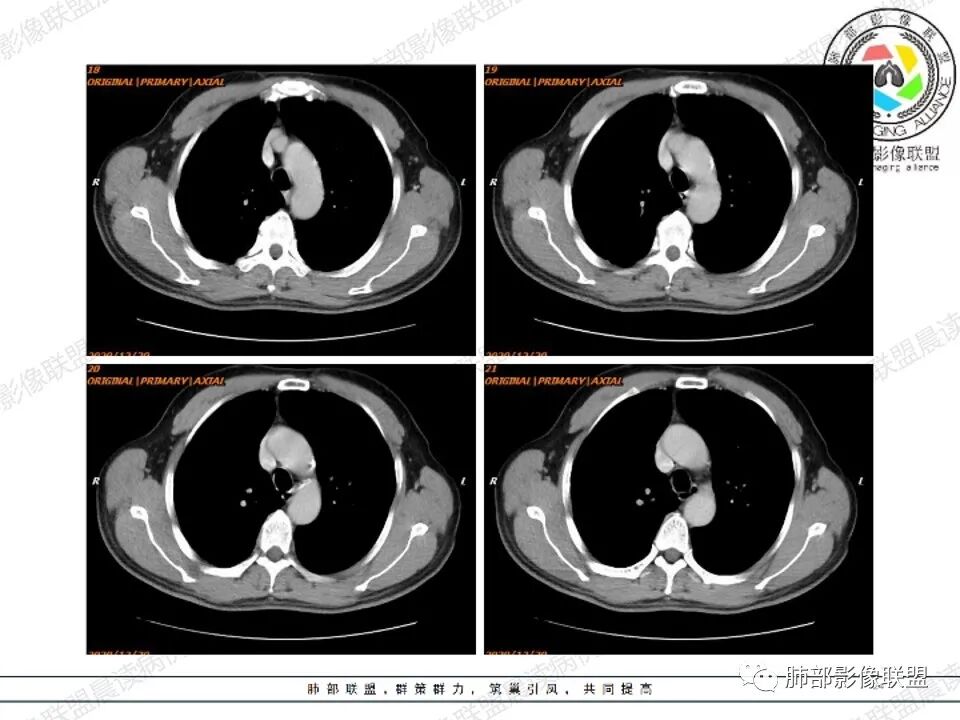

甄德强:

右肺上叶见一分叶状结节,增强扫描未见明显强化,考虑1.错构瘤2.支气管囊肿。

小强:

右上肺孤立性肿块性影,形态规则,边界清,密度25HU左右,没有点状钙化样密度,未见明确强化,周围可见条索,内缘肺透过度增强,有一副裂发育,考虑发育异常,支气管囊肿,CT值略高考虑合并感染;支气管闭锁,邻近未见明确支气管通行可排除;错构瘤,无强化应该是软骨型错构瘤,但是钙化太少,也可以排除;肿瘤,无强化可基本排除;结核球,不出除外

一切∮随缘:

右肺实性结节,形态欠规则,边缘光滑,彭隆,分叶,近端支气管未见显示,可能堵塞,平扫密度均匀,增强扫描,可见贴边血管,实性轻度强化,肿瘤标志物无明显增高,考虑支气管囊肿,错构瘤,

周太狼:

中年男性,右上肺类圆形肿块影,边缘膨隆,无明显分叶毛刺,内可见点状钙化,肿块整体密度较低,增强CT值才25HU左右(说明强化不明显或根本没有强化),周围可见少许斑片索条影,考虑良性病变,首选支气管囊肿,鉴别错构瘤。

滴水海:

看着血管被推移,张力大,应该是无强化,良性病变,支气管闭锁一般周围肺气肿明显,倾向支气管囊肿,鉴别畸胎瘤,CCAM